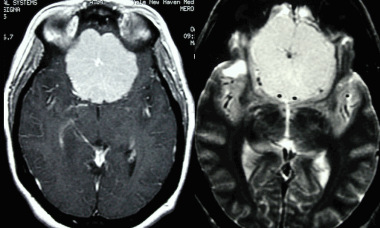

А: на Т1-взвешенном МР-изображении отмечается солидное образование, характеризующееся изоинтенсивностью по отношению к твердой мозговой оболочке, инвазией в кость и сдавлением теменных зон коры.

В: На Т1-взвешенном МР-изображении с контрастным усилением видна частично контрастируемая опухоль.

С: На корональном Т2-взвешенном изображении видно изоинтенсивное образование, что соответствует плотной ткани. Такая картина характерна для фибробластных менингиом.

D : На Т1-взвешенном МР-изображении с контрастным усилением визуализируется гиперинтенсивное образование внутри мозгового вещества кости.